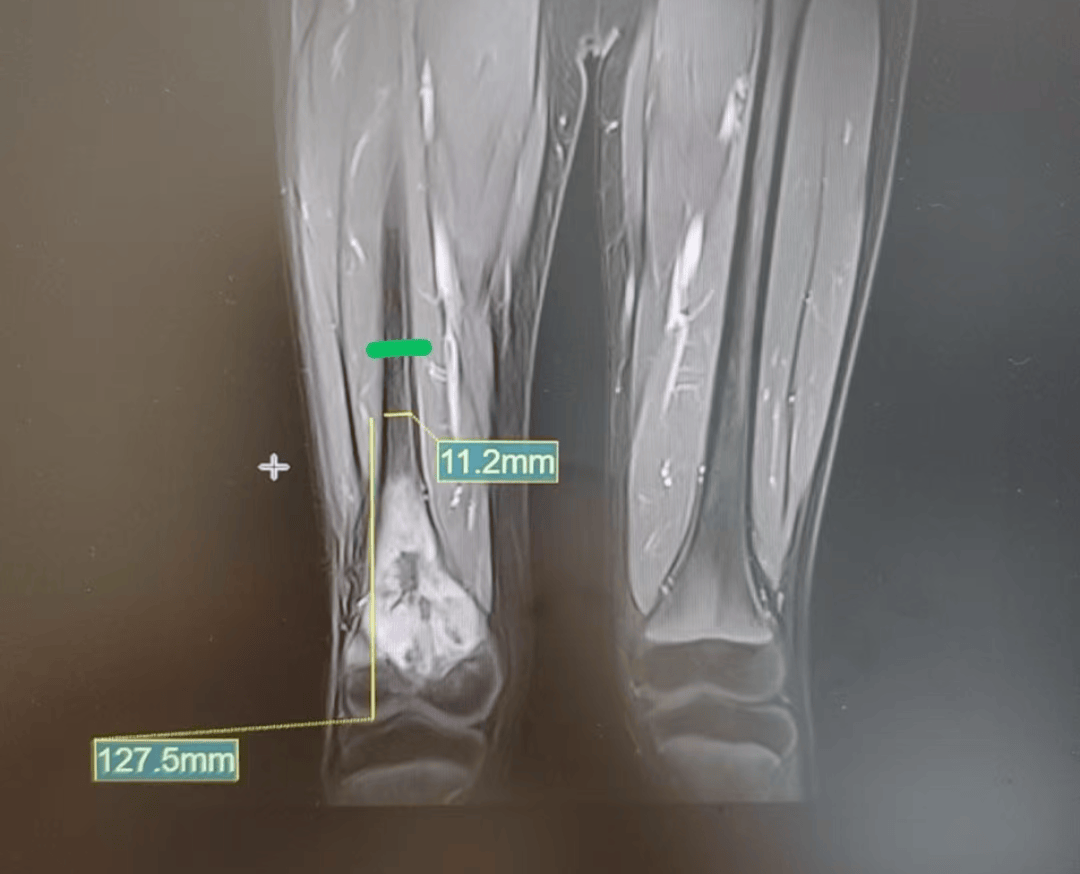

11岁男孩从2个多月前开始膝盖疼 本以为是生长痛,结果是骨癌…… 11岁的小宇是个活泼外向的男孩。两个多月前,他突然出现右膝盖疼痛的情况。 起初,疼痛并不明显,偶尔发作后也能自行缓解。看着孩子膝盖没有